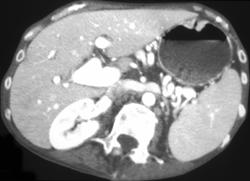

Ulcerating Colon Cancer With Colo-gastric Fistulae